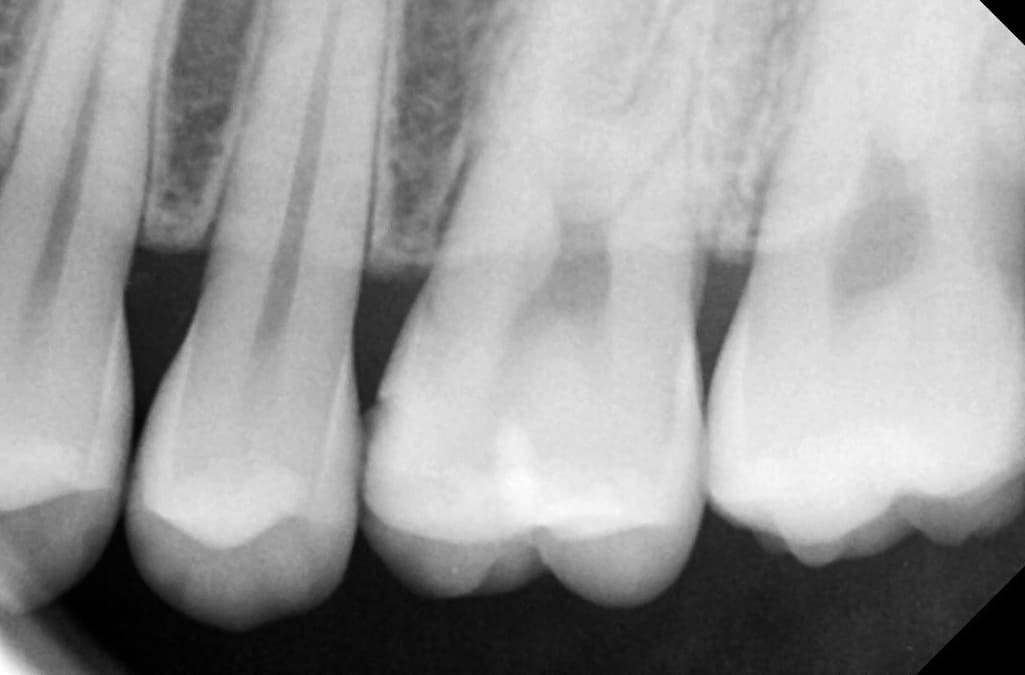

1치과는 충치가 있는 것 같다 양 옆 색상 차이가 있다 눈으로 확인 되는 정도라면 치료 해야 할 시기이다

위치 왼쪽 위 2번째 어금니 치료 한 부위 2차 충치

왼쪽 위 4번째와 3번째 사이 인접면 충치

사진에 보이는 정도면 충치가 안쪽에 많이 진행됫을 가능성이 있습니다. 저라면 인레이로 치료를 할것같습니다.

육안으로 보였을 경우 인절면에 충치가 있는 것으로 보입니다. 하지만 방사선상에는 크게 보이진 않습니다. 눈으로 보이는 충치가 있기 때문에 인접면 충치는 치료를 하는 것이 좋을 것으로 생각됩니다.

레진보다는 인레이를 하는 것이 일반적이며 레진은 술자를 잘 선택하셔야 합니다. 치료는 필요해보입니다.